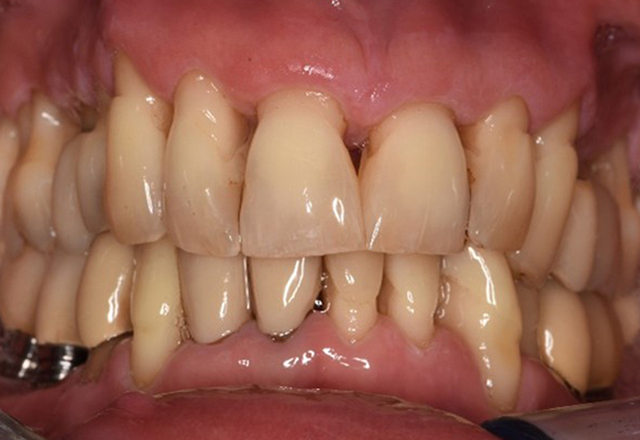

Die gesunde Patientin mit parodontaler Vorerkrankung